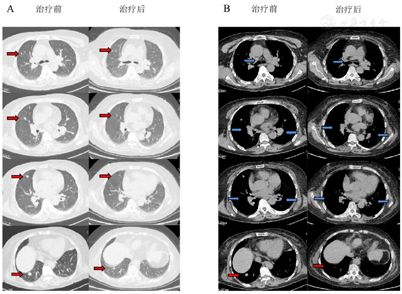

经过2个月的强的松治疗,嗜睡症状明显缓解,认知功能改善。复查头颅MRI示丘脑病变较前明显好转,复查胸部CT示双肺门、纵隔内多发肿大淋巴结及双肺结节均较前缩小。

脑磁共振成像(MRI)显示双侧大脑半球、右丘脑、右颞下叶多发病变(图1A)。胸部CT图像显示纵隔和双肺门淋巴结肿大并伴有多个肺结节(图2A)。18f -氟脱氧葡萄糖(FDG)正电子发射断层扫描(PET/CT)显示右上颈部深淋巴结、门部、纵隔、多发肺结节、双侧髋关节肌间隙、左髋关节皮下软组织明显摄取FDG(图3)。超声(US)引导下左髋关节皮下软组织活检显示大量嗜酸性粒细胞及纤维血管增生,无法提供诊断线索。然后我们在局部麻醉下对纵膈淋巴结进行WANG™经支气管抽吸针。然而,标本中仅发现少量纤毛柱状上皮细胞,诊断仍不明确。最后在全身麻醉下行支气管超声引导下经支气管针抽吸(EBUS-TBNA)纵隔淋巴结,发现慢性肉芽肿性炎症,提示结节病诊断(图4)。

文献报道,约5%至26%的结节病患者会出现神经系统并发症,在尸检研究中,患病率高达27%[6],这种累及神经系统的结节病,被称为神经系统结节病(Neurosarcoidosis, NS)。临床上,神经系统结节病的诊断往往依靠结节病多系统改变伴随神经系统表现,但必须先排除特殊病原菌感染及恶性肿瘤。由于神经系统结节病的组织学证据不易获得,因而当临床上怀疑神经系统结节病时,应先寻找神经系统以外疾病受累的证据。本病例以神经系统症状嗜睡起病,发病期间存在不规则发热,头颅MRI表现为右侧额叶、两侧颞叶、桥脑右侧、双侧基底节及侧室旁异常信号影,右侧丘脑病变伴周围水肿,胸部CT纵隔窗表现为双肺门、对称性淋巴结肿大,纵隔淋巴结肿大,胸部CT肺窗示表现为双肺散在多发结节,超声内镜引导下的经支气管针吸淋巴结活检提示慢性肉芽肿性病变,排除特异性感染后考虑结节病。该患者糖皮质激素治疗后未再出现发热,嗜睡及认知功能均较前明显改善,复查胸部CT示双肺门、纵隔内多发肿大淋巴结及双肺结节均较前缩小,复查头颅MRI示丘脑病变较前明显好转。故本病诊断肺结节病、神经系统结节病明确[7]。

约2/3神经系统结节病患者呈单相病程,另1/3呈复发-缓解病程或伴间歇性加重的进行病程[14]。与普通结节病患者相似,神经结节病患者预后较好,10年生存率为89%[15]。多数患者通过上述的治疗方法都可以控制病情、改善预后。但是长期接受糖皮质激素或免疫抑制药物等治疗可能诱发多种严重不良反应,如免疫功能严重受损或增加患癌的风险,故治疗过程中应定期随访、评估疗效、观察是否出现不良反应及并发症。本例患者诊断明确后依据共识使用激素治疗几天后其嗜睡、认知功能明显改善,2个月后嗜睡完全缓解,甲状腺功能趋向正常,胸部CT及头颅MRI提示病变较前好转,淋巴结较前缩小,故未进一步使用免疫抑制剂等治疗措施,患者转归及预后仍需进一步随访。